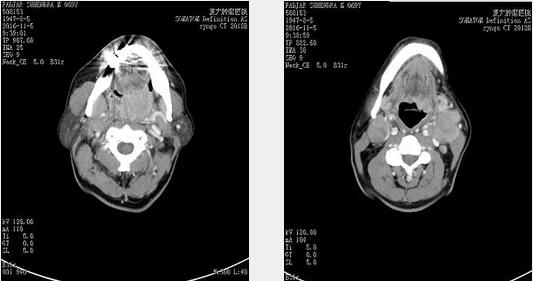

2016-11-05 CT:左侧扁桃体鳞癌,肿瘤侵犯舌根及会厌,口咽腔狭窄;双侧颌下、颈动脉鞘区及锁骨上区多发肿大淋巴结,考虑淋巴结转移,邻近双侧颈内静脉及肌肉受压变窄、粘连;

2016年11月5日治疗前CT 显示左侧扁桃体鳞癌,肿瘤侵犯舌根及会厌,口咽腔狭窄。